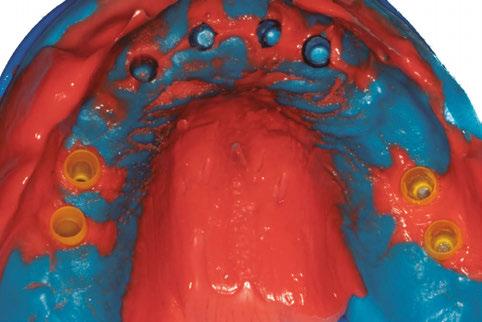

Protocolo Di2gitalArch® 2.0: Carga inmediata en el día en maxilar superior atrófico. Con Ziacom Galaxy, por el Dr. Luis Cuadrado Canals.